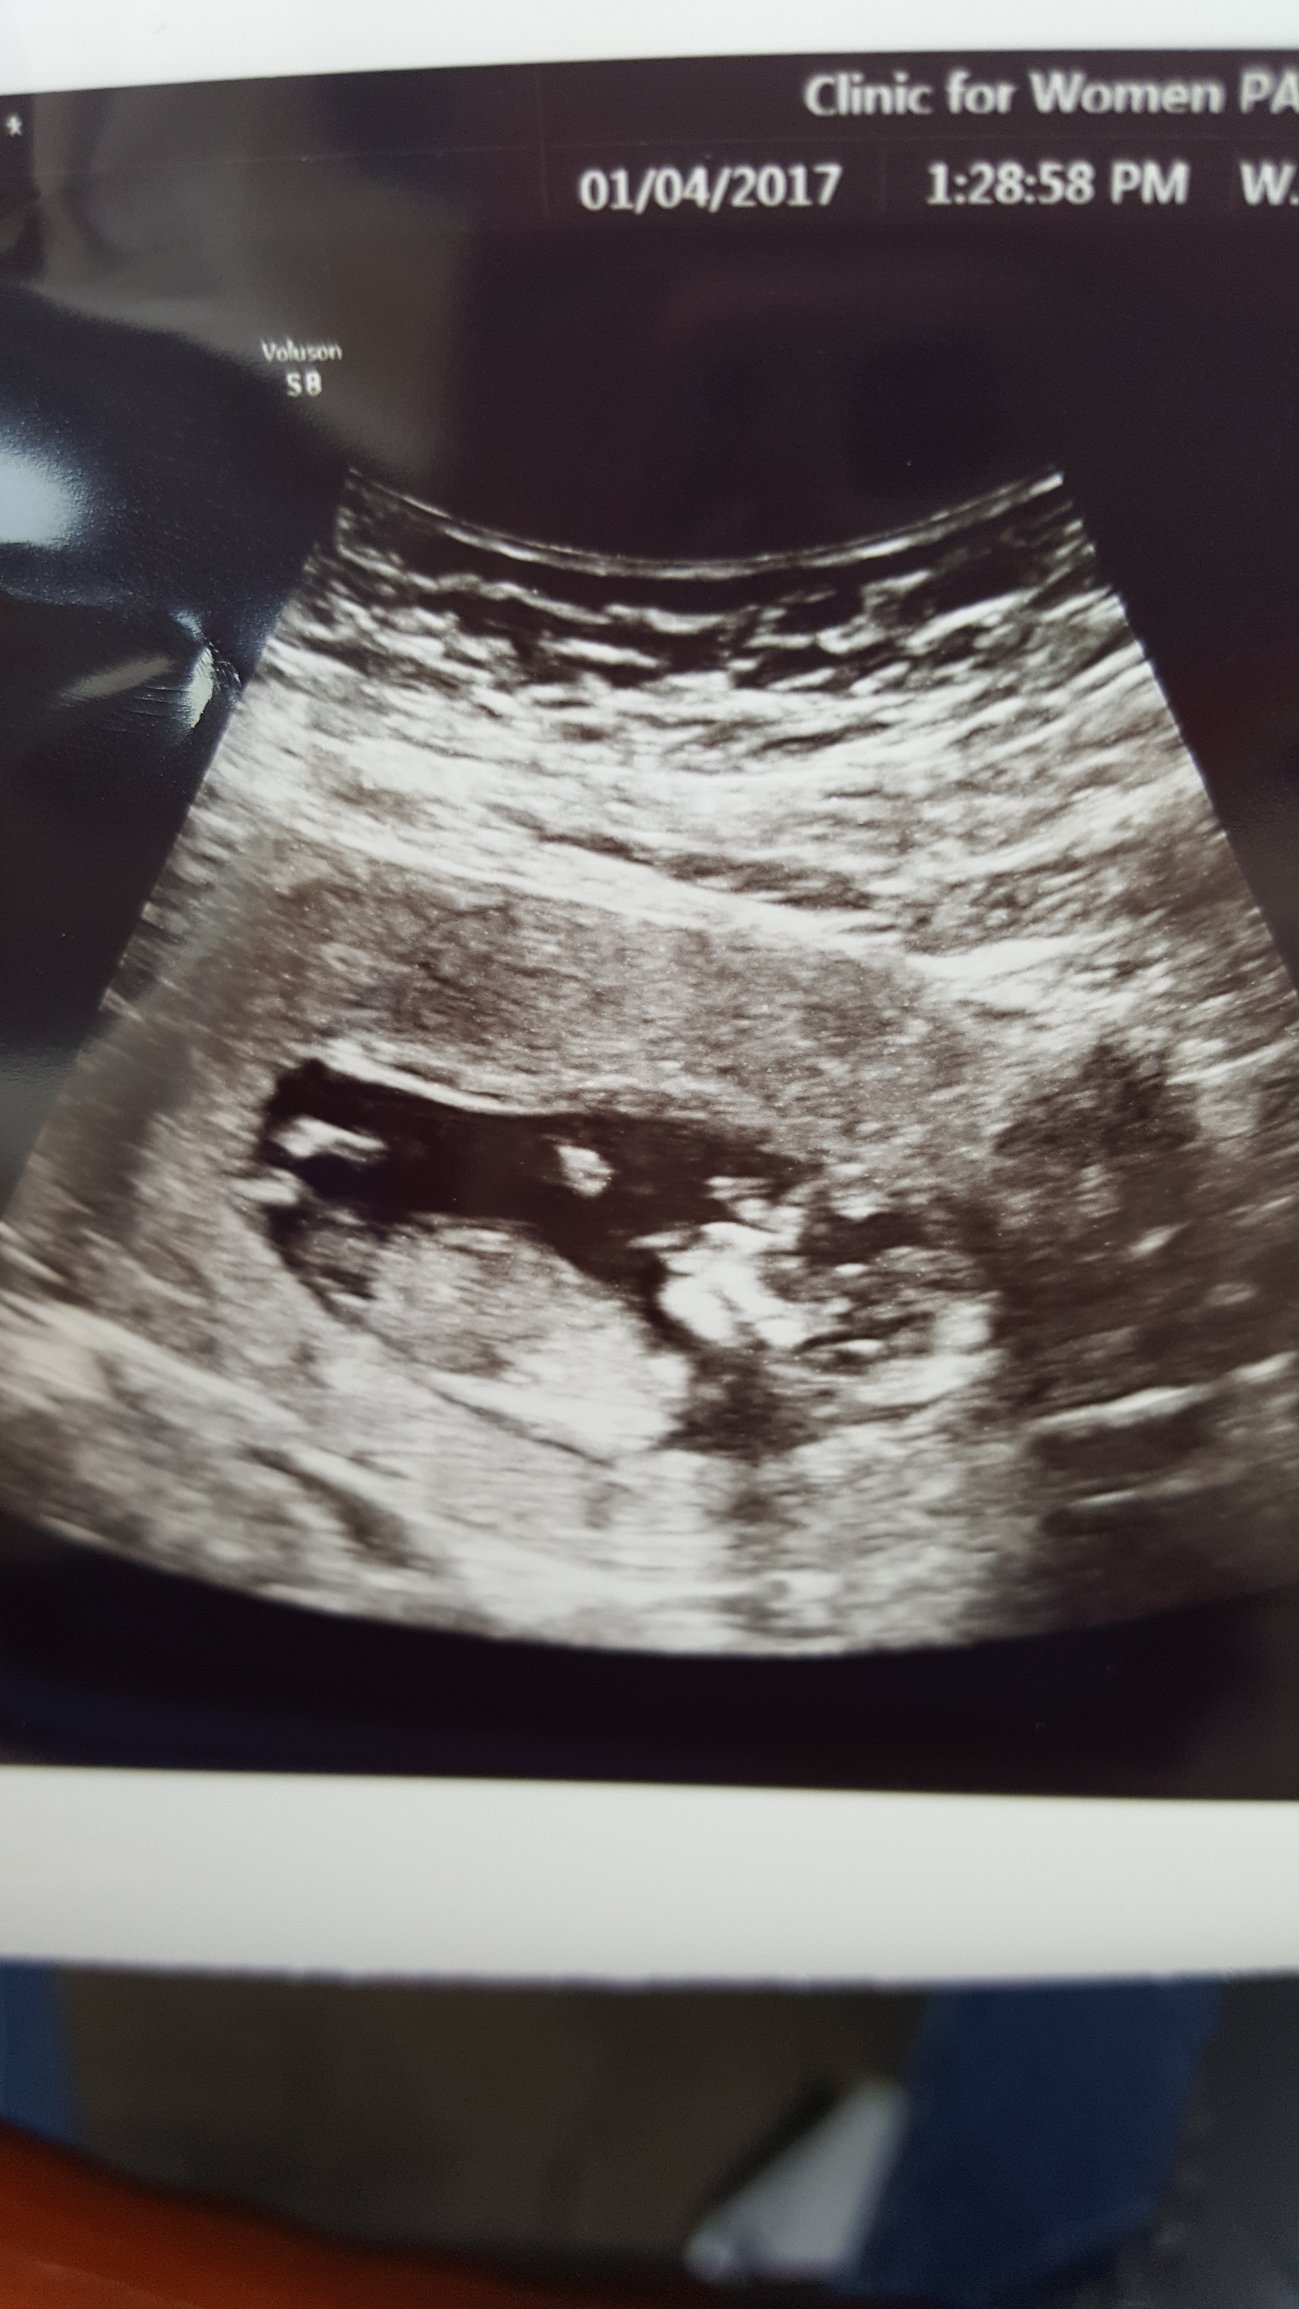

Tomorrow I go for my first prenatal appointment. While I am really excited about it, I'm also afraid that something is going to be wrong. Or that they'll find I'm having twins. I was part of identical triplets, but my sisters died shortly after birth. But mostly I'm worried something will be wrong, or that I'm totally crazy and am just growing one of those gigantic tumors in my uterus instead.

• @DarkSerendipity I hear you on that fear. My first appt was December 19, and I was a wreck going into it. Definitely thought I either wasn't pregnant (my symptoms have been really mild) or that I was having twins (fraternal twins run in my family). I can't remember if this is your first or not, but just know that you will feel relief after that appointment! Chances are, if you haven't had any severe cramping/bleeding, everything is just fine. And if it is twins? You will figure it out. Of course, I say all this knowing that before my appt, nothing ANYONE said would have helped, so take this with a grain of salt (and tell me to shove off, if need be :))!

• @RunRestRepeat LoL, thank you! I think I can tick off the no baby fear, because I did have to go to the ER at 10 weeks, and they confirmed a uterus monster with a heartbeat of 171. I just have to keep reminding myself of that.

• @DarkSerendipity I keep the ultrasound picture in my planner for that exact reason - I look at it every time I start to feel a bit of panic. Even though it was taken over two weeks ago, it still helps! Plus, if they did an u/s in the ER, they were able to confirm you aren't having twins, right?

• @RunRestRepeat That's the thing I can't quite remember - if the doc said 'baby' or 'babIES'. And I didn't get an ultrasound picture, which really sucks. But I didn't expect it.

• @DarkSerendipity Hmmmmm, that does leave a bit of mystery, doesn't it?! Fingers crossed everything goes perfectly at your appt tomorrow and there's one healthy bean! Keep us updated!

@DarkSerendipity - Congrats! <3

@DarkSerendipity did you mean to put your ultrasound photo in the Monday bitchfest?? I'm guessing you didn't...

Yeah, it is pertaining to earlier anxiety, so I feel that it is relative to this thread specifically because of that.

@DarkSerendipity so glad things turned out well, super happy, I hope looking at that pic helps when the anxiety starts to rise.